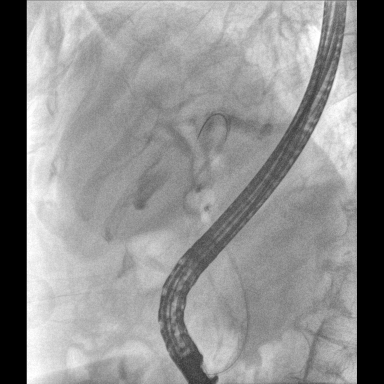

具備血管造影及數(shù)字減影(DSA)、路徑圖(Road-map)、透視、攝影等功能。 廣泛適用于介入科、血管外科、腫瘤科、消化內(nèi)科及骨科等多個(gè)臨床科室,典型應(yīng)用包括:TACE(肝腫瘤栓塞與化療灌注術(shù))、心臟起搏器置入術(shù)、四肢動(dòng)脈造影術(shù)、下肢靜脈濾器置入術(shù)、ERCP(經(jīng)內(nèi)鏡逆行胰膽管造影術(shù))等。

核心DSA軟件可實(shí)時(shí)生成高清血管影像,結(jié)合路徑圖功能,在手術(shù)中為醫(yī)生提供血管導(dǎo)航。

預(yù)留高壓注射器聯(lián)動(dòng)接口,C形臂開(kāi)始透視時(shí),高壓注射器自動(dòng)注入造影劑,提高術(shù)中造影減影效率,減少醫(yī)師手推造影劑所受到的輻射暴露劑量。